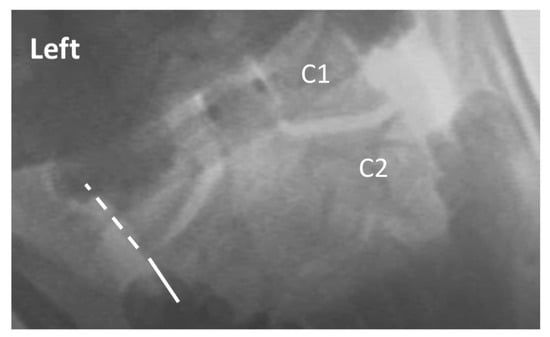

| Lateral overhang (AP) | C1-2 | A-P open mouth, R and L lateral flexion | Maximum difference in lateral translation (in mm) of the lateral margin of the lateral mass of C1 relative to the lateral margin of the superior articular facet of C2, between sides | 2 mm or less overhang difference between sides |

| Peri-odontoid space symmetry (AP) | C1-2 | A-P open mouth, R and L lateral flexion | Bilateral symmetry of gap between dens of C2 and medial margin of lateral mass of C1, observed at extreme R and L flexion | Symmetrical gap maintained |

| C1-2 lateral overhang (AP view) | 0–2 mm | 0–2 mm > 2 mm |

| > 2–4 mm | ||

| > 4–6 mm | ||

| > 6 mm | ||

| C1-2 peri-odontoid symmetry (AP view) | Symmetrical | Symmetrical Asymmetrical |

| Mildly-Asymmetrical | ||

| Asymmetrical | ||